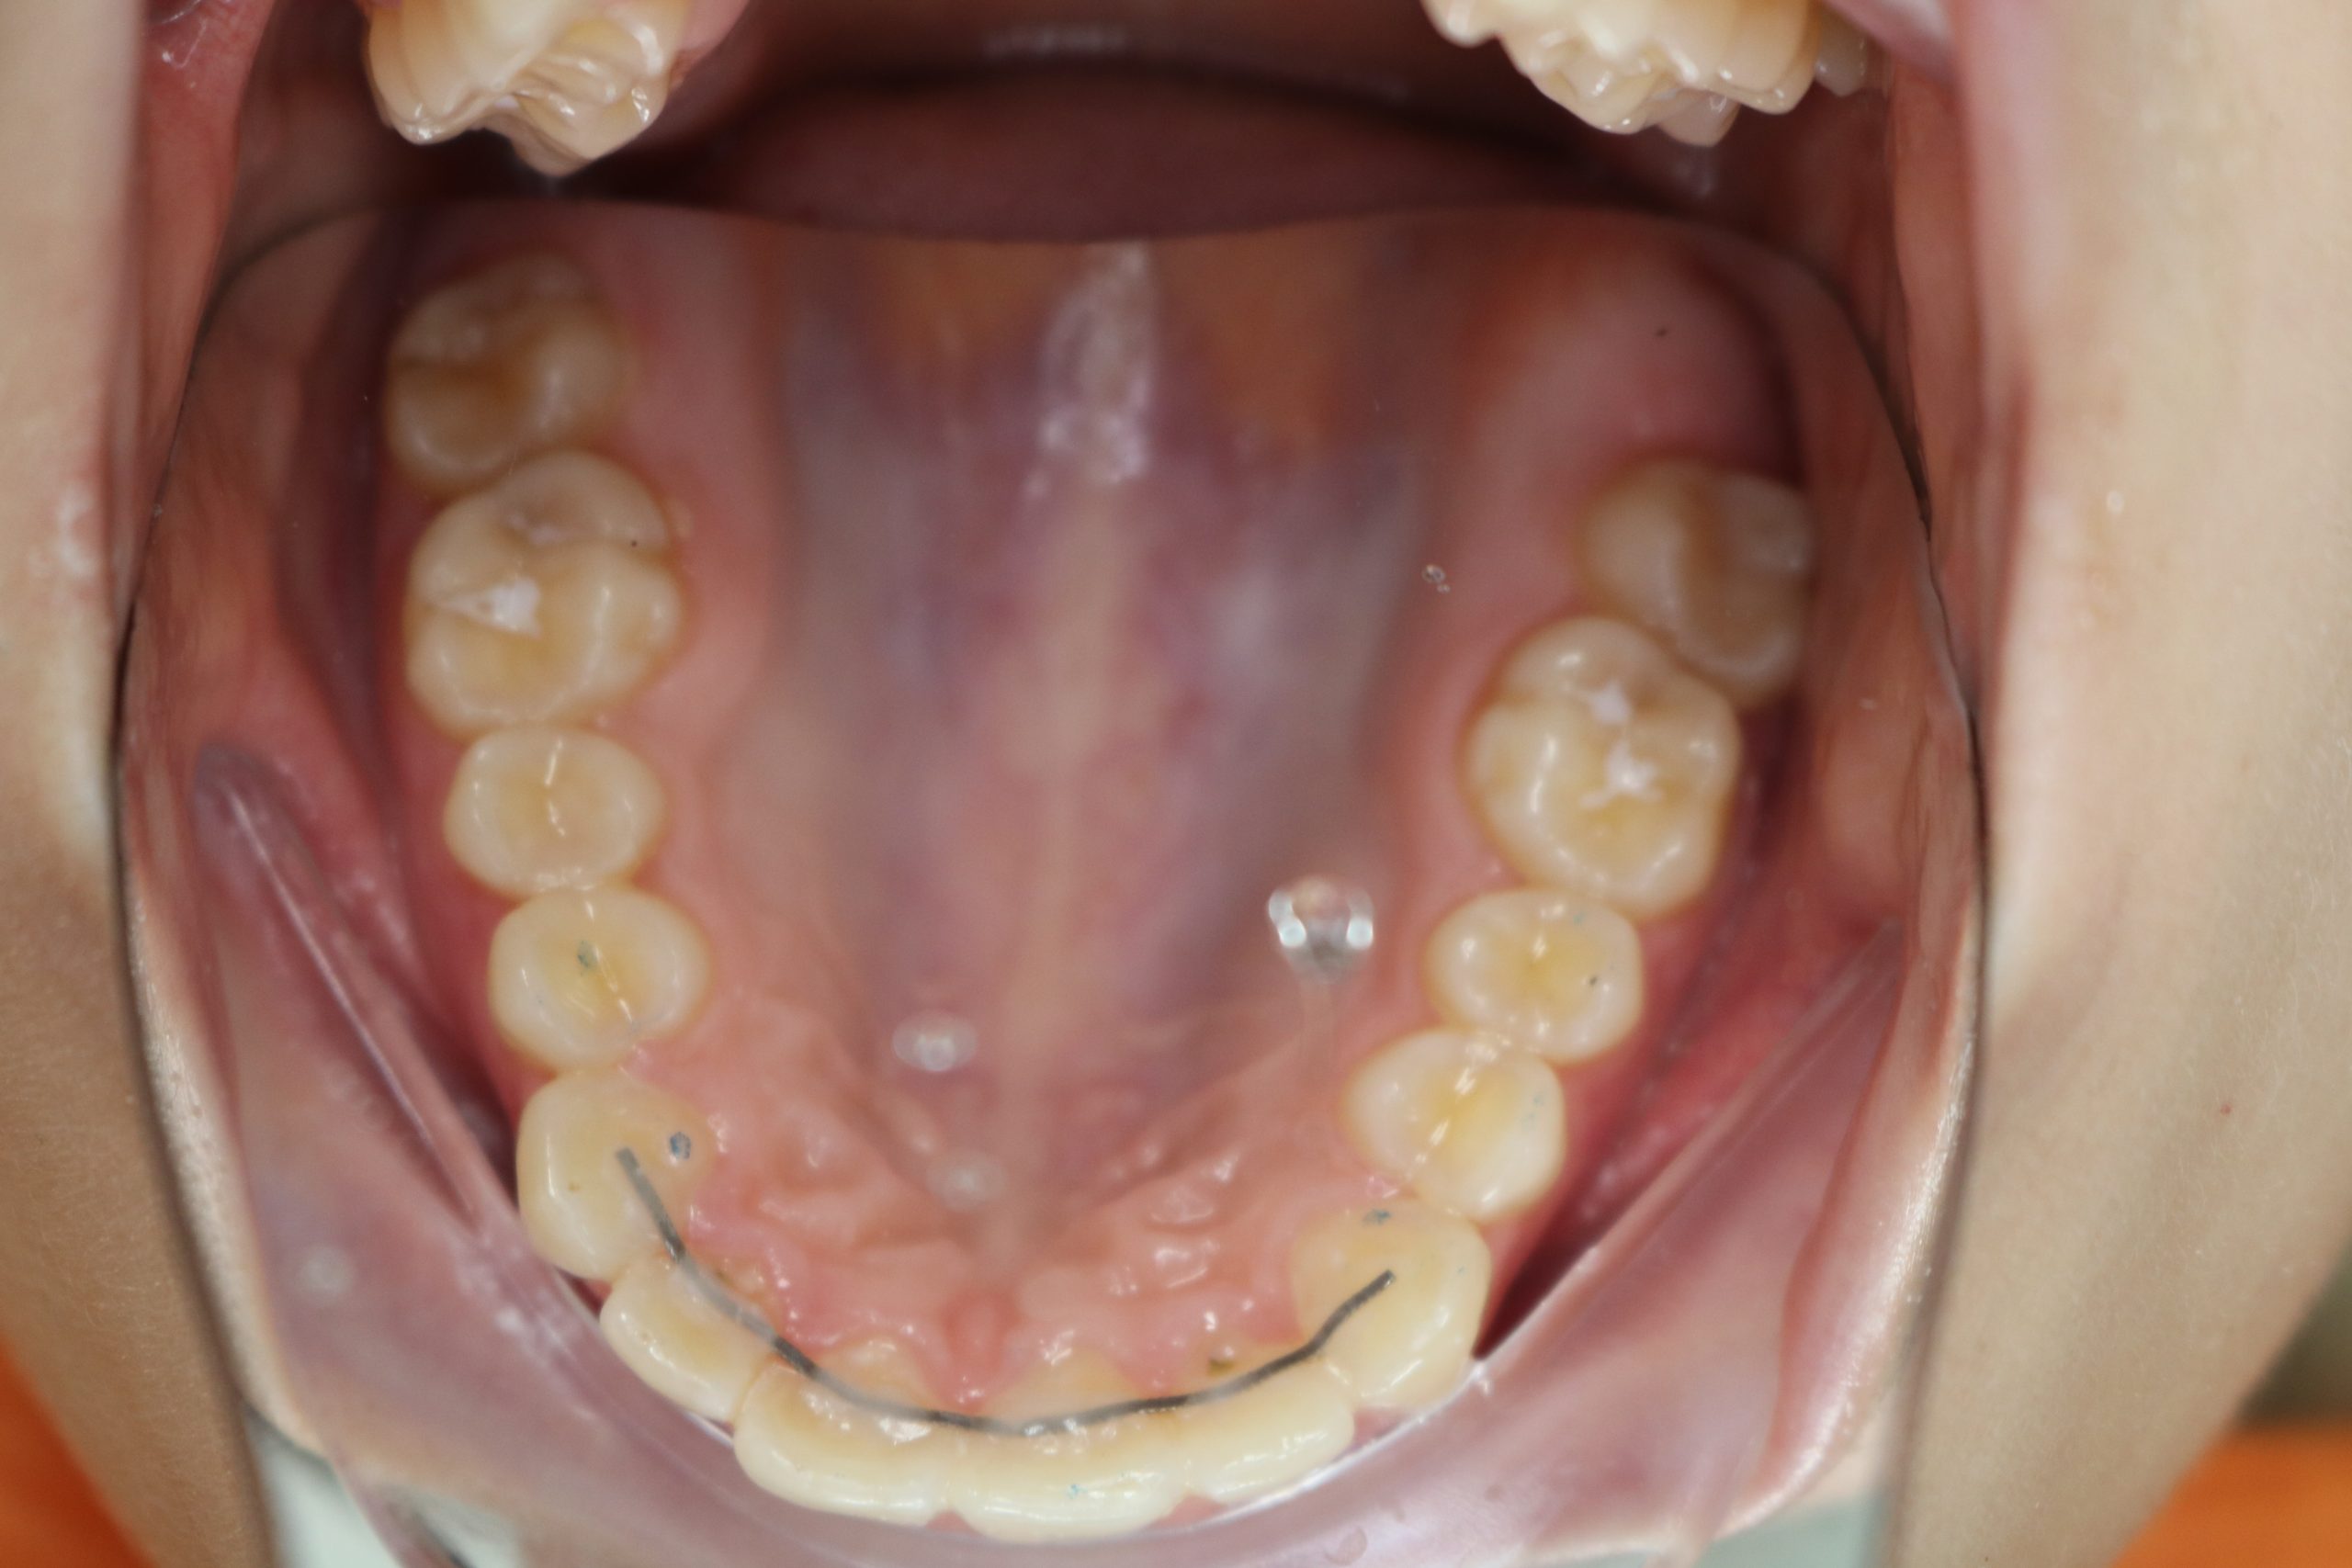

Точная и своевременная диагностика является ключевым фактором успешного лечения пародонтита․ Современные методы диагностики позволяют не только определить стадию заболевания‚ но и оценить его активность‚ а также выявить скрытые очаги воспаления․ К ним относятся⁚

- Компьютерная томография (КТ)⁚ позволяет получить трехмерное изображение челюстей‚ что дает возможность детально оценить состояние костной ткани и выявить даже незначительные дефекты․

- Цифровая рентгенография⁚ обеспечивает более качественные и безопасные изображения‚ чем традиционная рентгенография․

- Тесты на определение уровня бактериальных биомаркеров в слюне⁚ позволяют оценить активность воспалительного процесса и предсказать эффективность лечения․

- Анализ микробиоты полости рта⁚ позволяет определить видовой состав бактерий‚ вызывающих пародонтит‚ что важно для выбора индивидуальной схемы лечения․

Благодаря применению этих современных методов диагностики‚ врачи могут составить более точный план лечения‚ учитывающий индивидуальные особенности каждого пациента․